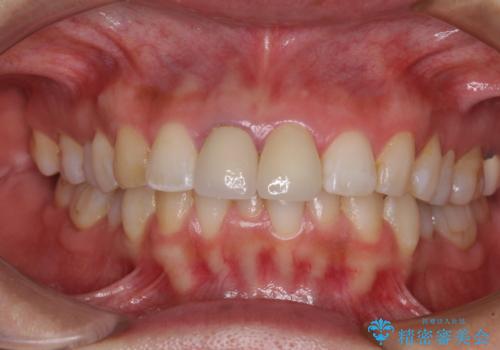

目立つ前歯の詰め物 オーダーメイドのセラミッククラウンで審美的に仕上げる

反対側同名歯にセラミッククラウンが装着されていたため、そちらのクラウンと形態や色彩を揃えるようオーダーメイドタイプのオールセラミッククラウンにて補綴することとしました。

2本同時に処置をし、2本とも明るい色合いにすることをお勧めしましたが、今回は1歯のみとしました。

左右のバランスが取れ、患者様には大変満足していただきました。